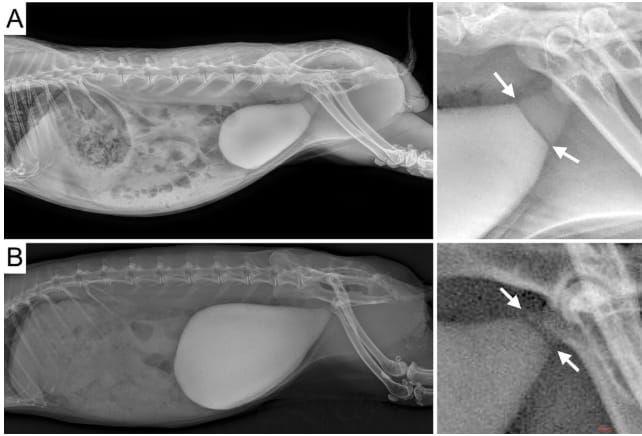

A and B—Representative lateral abdominal radiographs of rabbits diagnosed with a septum at the level of the urinary bladder neck, developing on the dorsoventral/laterolateral plane, and urinary bladder sludge for case 1 (A) and case 6 (B). Images magnified and increased in contrast are provided for better visualization of the septum (arrows) on the right of the original radiographs. The septum is visible as a filling defect in the urinary sludge.